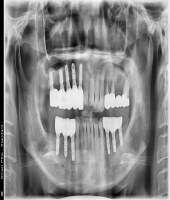

● 진료과목 : [임플란트] 충치 및 치주질환 임플란트

● 내용 : 충치와 치주질환에 의한 치아상실로 임플란트 치료함.